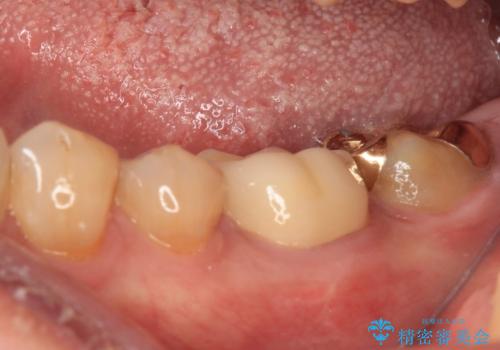

1番奥は歯肉に覆われている部分が大きいため、欠損部とむし歯の部分をゴールドインレーにて修復し、手前の歯はオールセラミッククラウンにて補綴治療を行うこととしました。

来院前から痛みはありませんでしたが、食事の度にものが挟まる不快感がありました。

処置後はスッキリとした環境になりました。